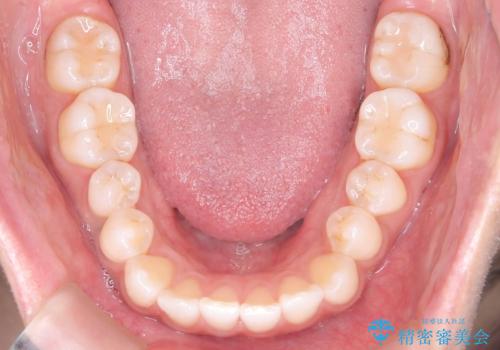

- 歯の捻じれやデコボコを主訴にご来院された患者様です。

矯正治療の精密検査を行った結果、非抜歯(歯を抜かない)矯正治療を選択いたしました。